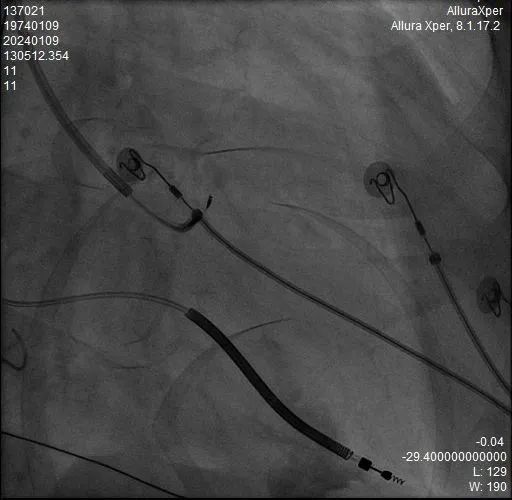

术中HIS电极影像

LBB影像位置

术中影像 HIS-HISD-消融靶点